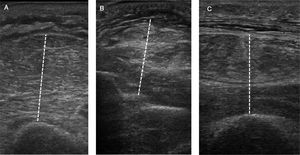

Técnica. Diversos sitios anatómicos y variantes técnicas han sido empleados para la evaluación muscular periférica, dificultando la comparación de resultados entre los distintos estudios. Si bien valores de referencia para grosor y ecogenicidad se han reportado en individuos sanos, la evolución temporal de los mismos parece ser un parámetro más valioso en pacientes críticos84. Es fundamental identificar y estandarizar precisamente el sitio y posición en donde se realizará la medida. Es importante evitar la compresión del músculo durante la medida, para lo cual debe emplearse un exceso de gel conductor y realizar con el transductor la mínima presión que permita obtener la imagen.

Los registros se obtienen con un transductor lineal (≥ 10MHz) posicionado en sentido transversal y perpendicular al hueso subyacente. El ángulo de insonación puede afectar a las medidas, por lo que debe mantenerse constante. El grosor se mide como la máxima distancia entre la interfase grasa-músculo y el hueso o membrana interósea (fig. 2). En la tabla 3 se detalla la técnica para brazo, antebrazo y muslo33,73,85,86.

Protocolo de ecografía muscular periférica

| Brazo | Con el codo flexionado a 90° se debe buscar el punto equidistante entre el acromion y el olécranon. Posteriormente, con el codo extendido y el antebrazo supinado, colocar el transductor lineal en la cara anterior, a nivel del punto medio previamente identificado. Posicionar el transductor en sentido transversal y perpendicular a la piel. Medir, en el sitio de máximo espesor, el compartimento muscular flexor entre la interfase grasa-músculo y el húmero |

| Antebrazo | Con el codo extendido y el antebrazo supinado identificar el punto equidistante entre el pliegue del codo y la apófisis estiloides cubital. Colocar el transductor lineal en la cara anterior sobre dicho punto, en sentido transversal y de forma perpendicular a la piel, midiendo el espesor del compartimento flexor entre la interfase grasa-músculo y la membrana interósea |

| Muslo | Con la rodilla extendida, marcar el punto equidistante entre el trocánter mayor y la línea articular de la rodilla. Colocar el transductor lineal en la cara anterior sobre dicho punto, en sentido transversal y de forma perpendicular a la piel. Medir el espesor del grupo muscular del cuádriceps a este nivel como la distancia entre la interfase grasa-músculo y el fémur. La medida del AST del recto femoral se obtiene mediante técnica planimétrica, luego de delimitar su margen interno (línea ecogénica) con el cursor |